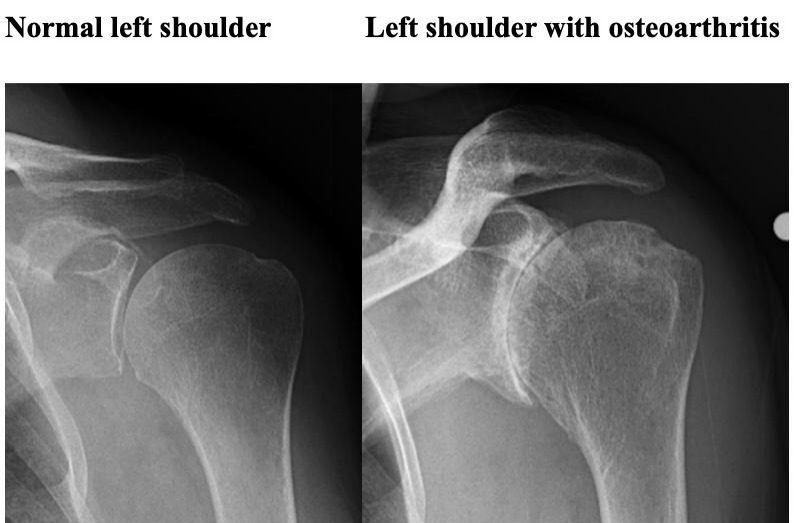

- Osteoarthritis Also called “wear-and-tear” arthritis Caused by gradual cartilage degeneration More common after age 50 Often affects the AC joint, but glenohumeral arthritis causes more symptoms

- X-rays

- Joint space narrowing

- Bone spurs

- Joint deformity